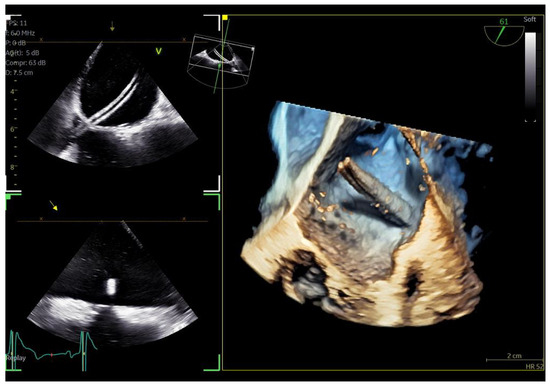

The adult probe was initially inserted for complete 2D/4D image acquisition, followed by the insertion of the pediatric probe while the patient remained under sedation. Remarkably, insertion of the pediatric probe was effortless in all cases, requiring no additional sedation. Despite encountering challenging diagnostic scenarios in all three cases (1st patient: combined severe aortic stenosis and severe mitral regurgitation (MR) due to P1 scallop prolapse, 2nd patient: malfunction of metallic mitral valve prosthesis with an occluded disk, 3rd patient: bioprosthetic aortic valve with paravalvular leak and significant MR in previously MV repair with a complete ring), the pediatric probe consistently provided high-quality images comparable to those obtained with the standard adult probe (Figure 1 and Figure 2, video S4). Notably, there was no compromise in 2D and 4D spatial and temporal resolution, with only minor differences observed compared to the adult 6VT-D probe (Table 1). Evaluation using the 5-point scoring system consistently yielded an average score close to 5 for all three cases, indicating excellent image quality (Table 1).

Figure 2.

Direct comparison of 3D volume-rendered “en face” images of a metallic prosthetic mitral valve with occluded disk. Left image corresponds to 6VT−D adult probe and right image corresponds to 9VT−D pediatric probe. Images enhanced with “photorealistic method” with Flexilight application (GE Healthcare).